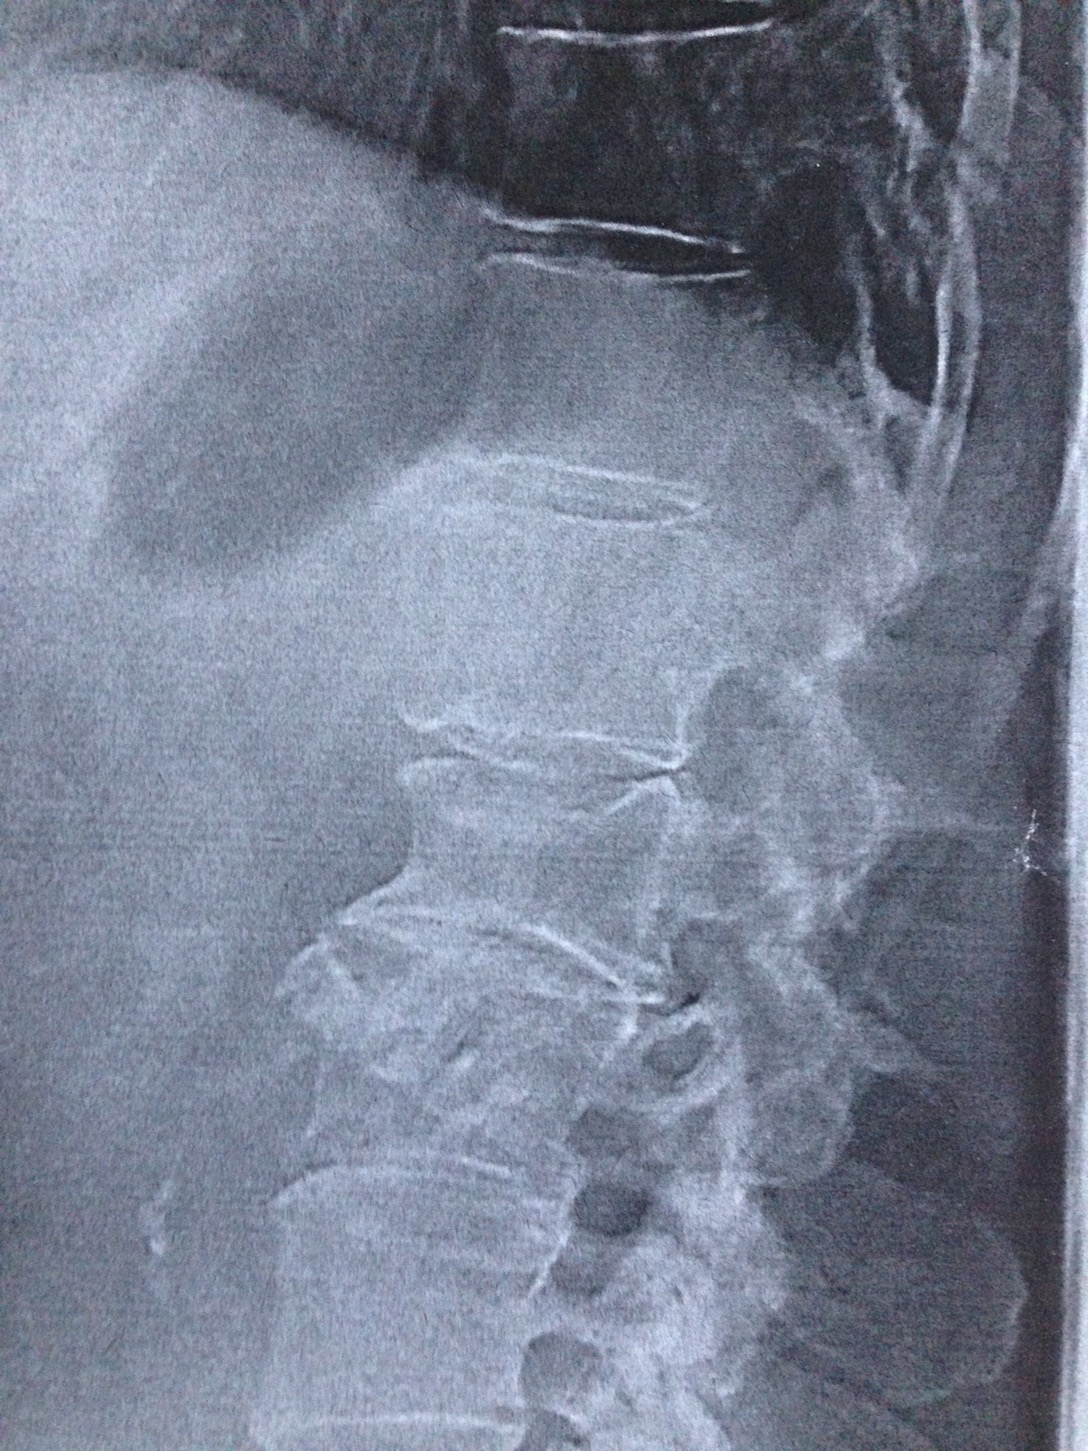

Ich war vorhin bei einem anderen Arzt, also mit dem ich früher mal gute Erfahrungen gemacht habe. Der war viiel besser als der erste im März. Der erste hat kaum untersucht, mich nur zum Röntgen geschickt und dann Physiotherapie verschrieben, wo die Übungen und die Massage letztlich nichts gebracht haben. Der heutige Arzt hat genau untersucht (öfter vorbeugen und er tastet ab etc.). Ich habe von ihm eine Doppelübung bekommen, die ich morgens und abends machen soll. Ich habe das Gefühl, die ist genau richtig: